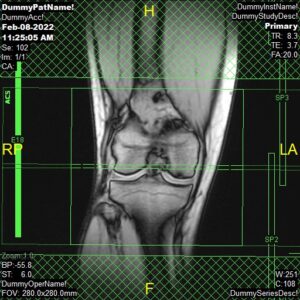

T1 Flair/Tirm Coronal, PD Coronal and PD FatSat Coronal

Parameters

Sample Image